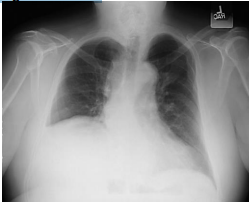

Paciente de 66 anos é avaliado no pronto-socorro por quadro de dor precordial. Refere que dor é em pontada na região esternal, irradiada para dorso, de forte intensidade. Havia se iniciado ao repouso e teve duração de 40 minutos. Antecedentes pessoais: Hipertensão arterial, em uso de Anlodipino. Ao exame físico: Afebril, Frequência cardíaca de 110 batimentos por minutos e Pressão arterial de 180/80 mmHg em ambos os membros. Ausculta respiratória sem alterações. Impulso carotídeo normal, pressão venosa jugular normal, B1 e B2 normais, sopro diastólico aspirativo 2+/6+ em rebordo esternal esquerdo.

Exames laboratoriais com CKMB: 8 (Valor Referência <5) e Troponina 0,5 (Valor Referência < 0,09). Eletrocardiograma: Taquicardia sinusal e alteração não específica da onda T e do segmento ST na parede lateral Radiografia de tórax:

Considerando a principal hipótese diagnóstica, assinale a alternativa que apresenta qual seria o melhor exame a ser realizado neste momento.